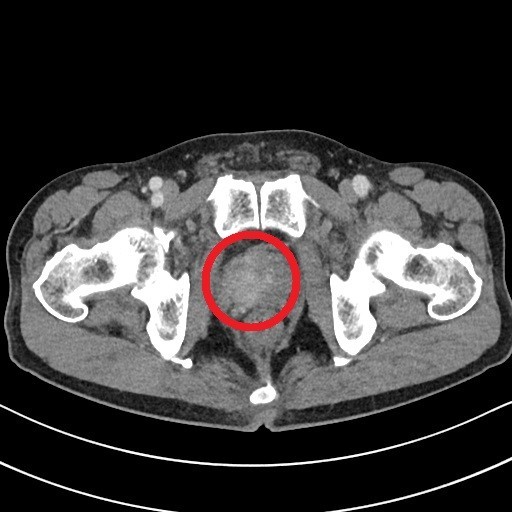

남자의 요도가 시작되는 부위를 둘러싸는 생식 기관입니다. 전립선은 전립선액을 만들어 정자에게 영양을 공급해 준다. 요도와 사정관을 둘러싸서 방사성으로 배열하는 30~50개의 복합관상 포상선이 집합해 있습니다.

전립선암이란?

전립선에서 발생하는 암을 말하며, 대부분 전립선 세포에서 발생하는 샘세포의 암입니다. 기능에 고장이 생긴 세포는 죽지 않고 종괴를 형성할 수 있습니다. 이 종괴는 양성 종양과 악성 종양으로 나뉘는데, 전립선암은 악성 종양입니다. 참고로 전립선비대증은 양성 종양입니다.